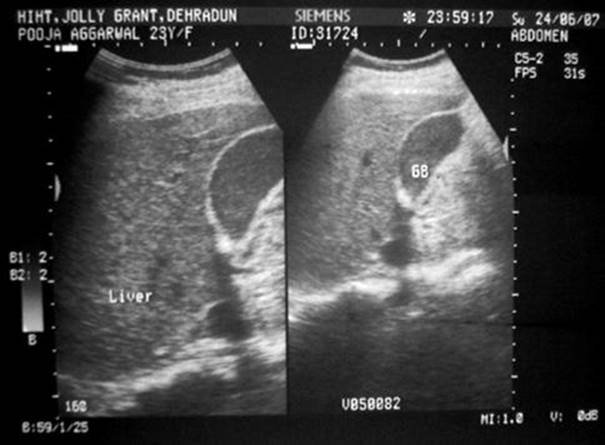

Imaging in pregnancy remains a controversial issue with concern of the effect of radiation on the developing fetus. Abdominal ultrasound (US) with no radiation to the fetus is the initial imaging technique of choice to identify or exclude biliary etiology, the finding on which further therapy depends (Fig. 3.6). However, it is insensitive for the detection of common bile duct stones or sludge and the morphological changes of the pancreas. It is not accurate for detection of dilated pancreatic ducts but is good for pseudocysts and focal accumulations larger than 2–3 cm. US is limited by operator skill, patient obesity, and bowel dilation especially found in patients with peritonitis. Additional abdominal US role is for estimation of fetal vitality by measuring direct (femur) or indirect parameters (oligohydramnios) (Fig. 3.7).

Fig. 3.6

Abdominal ultrasound of the abdomen showing gallbladder sludge in a 23-year-old nulliparous woman in 33 weeks of pregnancy [288]

Fig. 3.7

Sonography of the same patient as in Fig. 3.6 showing femur length of 61.4 mm corresponding to 33 weeks of gestation with oligohydramnios [288]